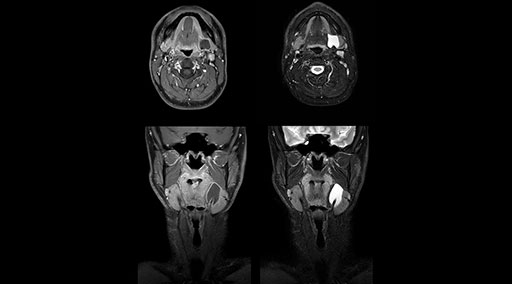

mDIXON TSE fat suppression helps DMG reduce repeats and supports diagnostic confidence

“Our DMG Lisle location includes a cancer center, so soft tissue neck scans, brachial plexus scans, and prostate scans are common. For these exams, mDIXON TSE provides excellent images with and without fat suppression all while helping us reduce repeats and work more efficiently,” Mr. Duffy says.

“With the 2-echo Philips mDIXON TSE the timing is short and the fatsat is very robust. The biggest thing is that you know your fat suppression will be good, even in thin patients or large patients that are off-center,” Mr. Sybesma says.

“Since we work in fixed time slots, not having to repeat scans is key for us,” Mr. Duffy adds. “With mDIXON TSE we get high quality results the first time – unless of course the patient absolutely jumps off the table. For us, that’s significant, because just a single repeat scan could put us behind schedule.

“mDIXON TSE raises our diagnostic confidence with its homogeneous

fat suppression. Neck exams and rheumatology patients are two examples where mDIXON TSE is especially useful,” Dr. Kaakaji says. “For us it’s also an efficiency boost in exams where we need pre and post T1-weighted images with great fat suppression.”

“mDIXON TSE raises our diagnostic confidence with its homogeneous fat suppression”